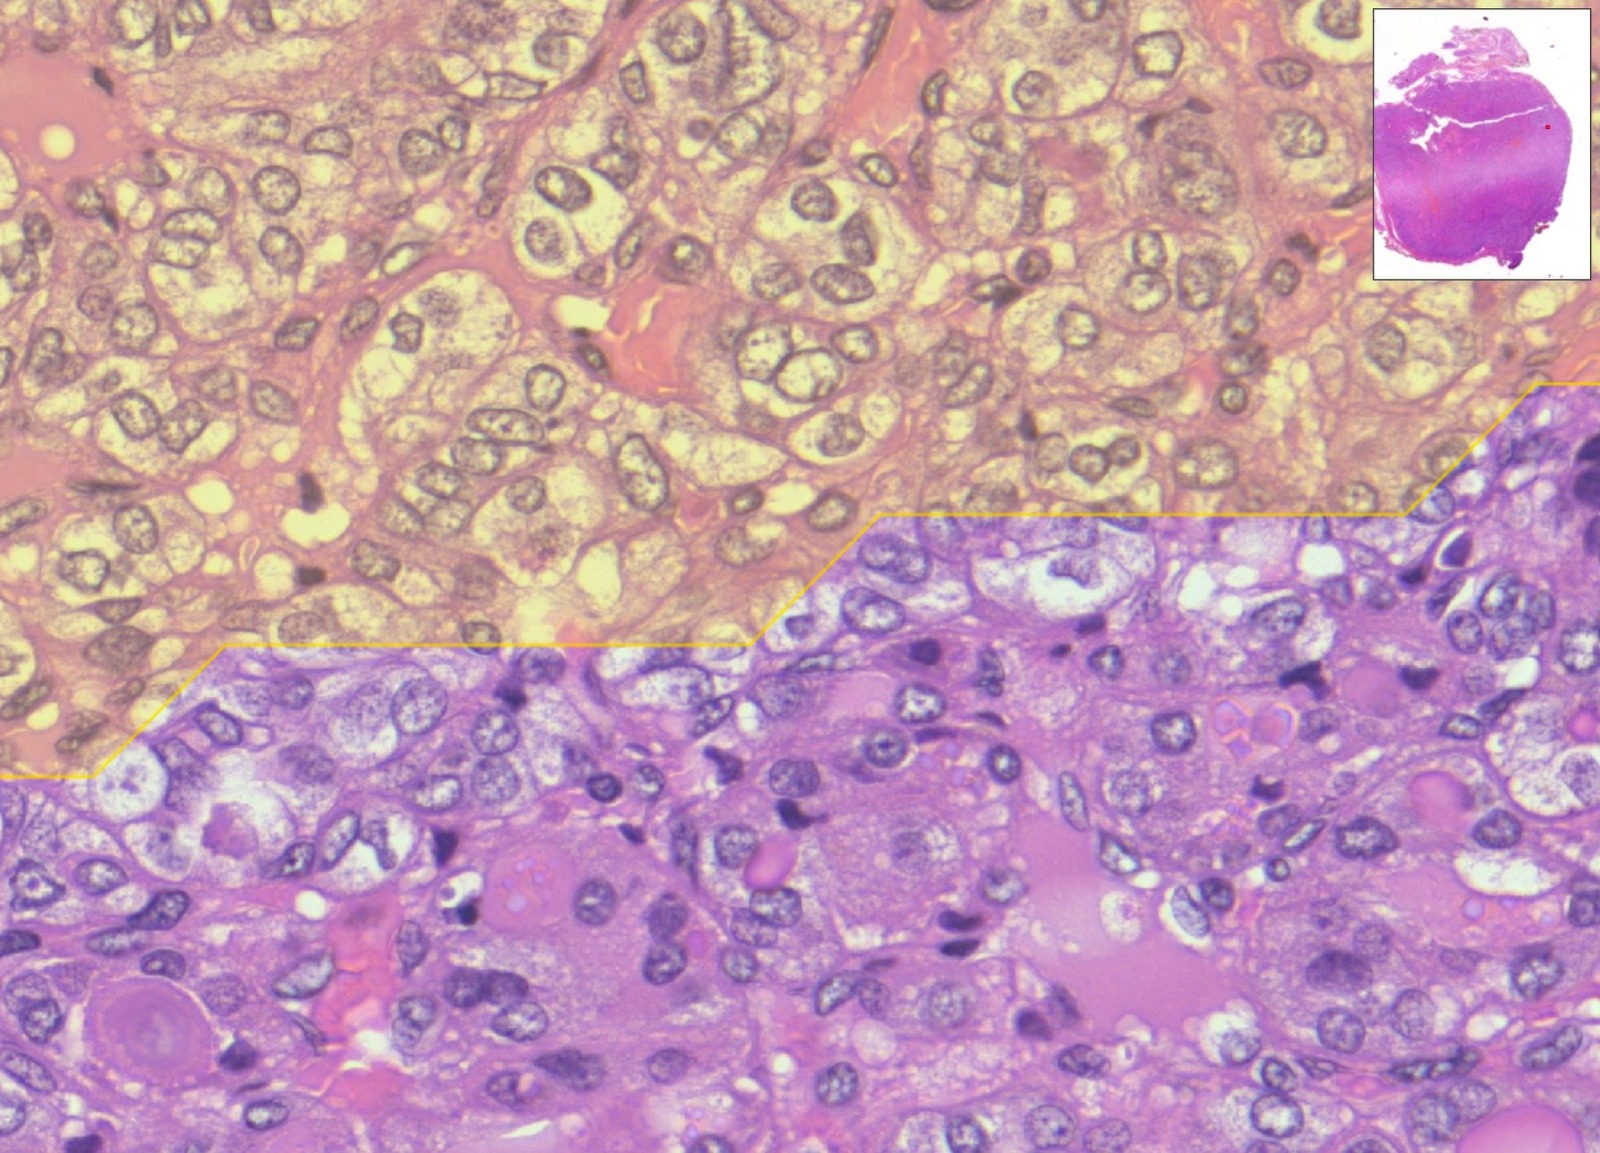

Si tratta di un algoritmo di digital pathology capace di analizzare immagini istologiche ad altissima risoluzione in grado di fornire un aiuto significativo ai medici nella diagnosi di tumori.

Il sistema utilizza reti neurali profonde (strumenti di deep learning, dunque basate sull’Intelligenza Artificiale) addestrate su migliaia di campioni digitalizzati con scanner molto potenti (l’immagine ricavata dai vetrini istologici su cui si trovano le cellule da analizzare) per identificare automaticamente aree, cellule, marcatori sospetti, spesso difficili da rilevare da parte dell’occhio umano.

Più nello specifico, il sistema sviluppato nella ricerca mette in campo un “doppio occhio”, due reti neurali che lavorano in sequenza: un primo “occhio digitale” coglie i dettagli delle cellule, un secondo “occhio” considera la visione d’insieme dell’immagine. Integrando le due letture, MiThyCA indica le aree che è opportuno analizzare per prime.